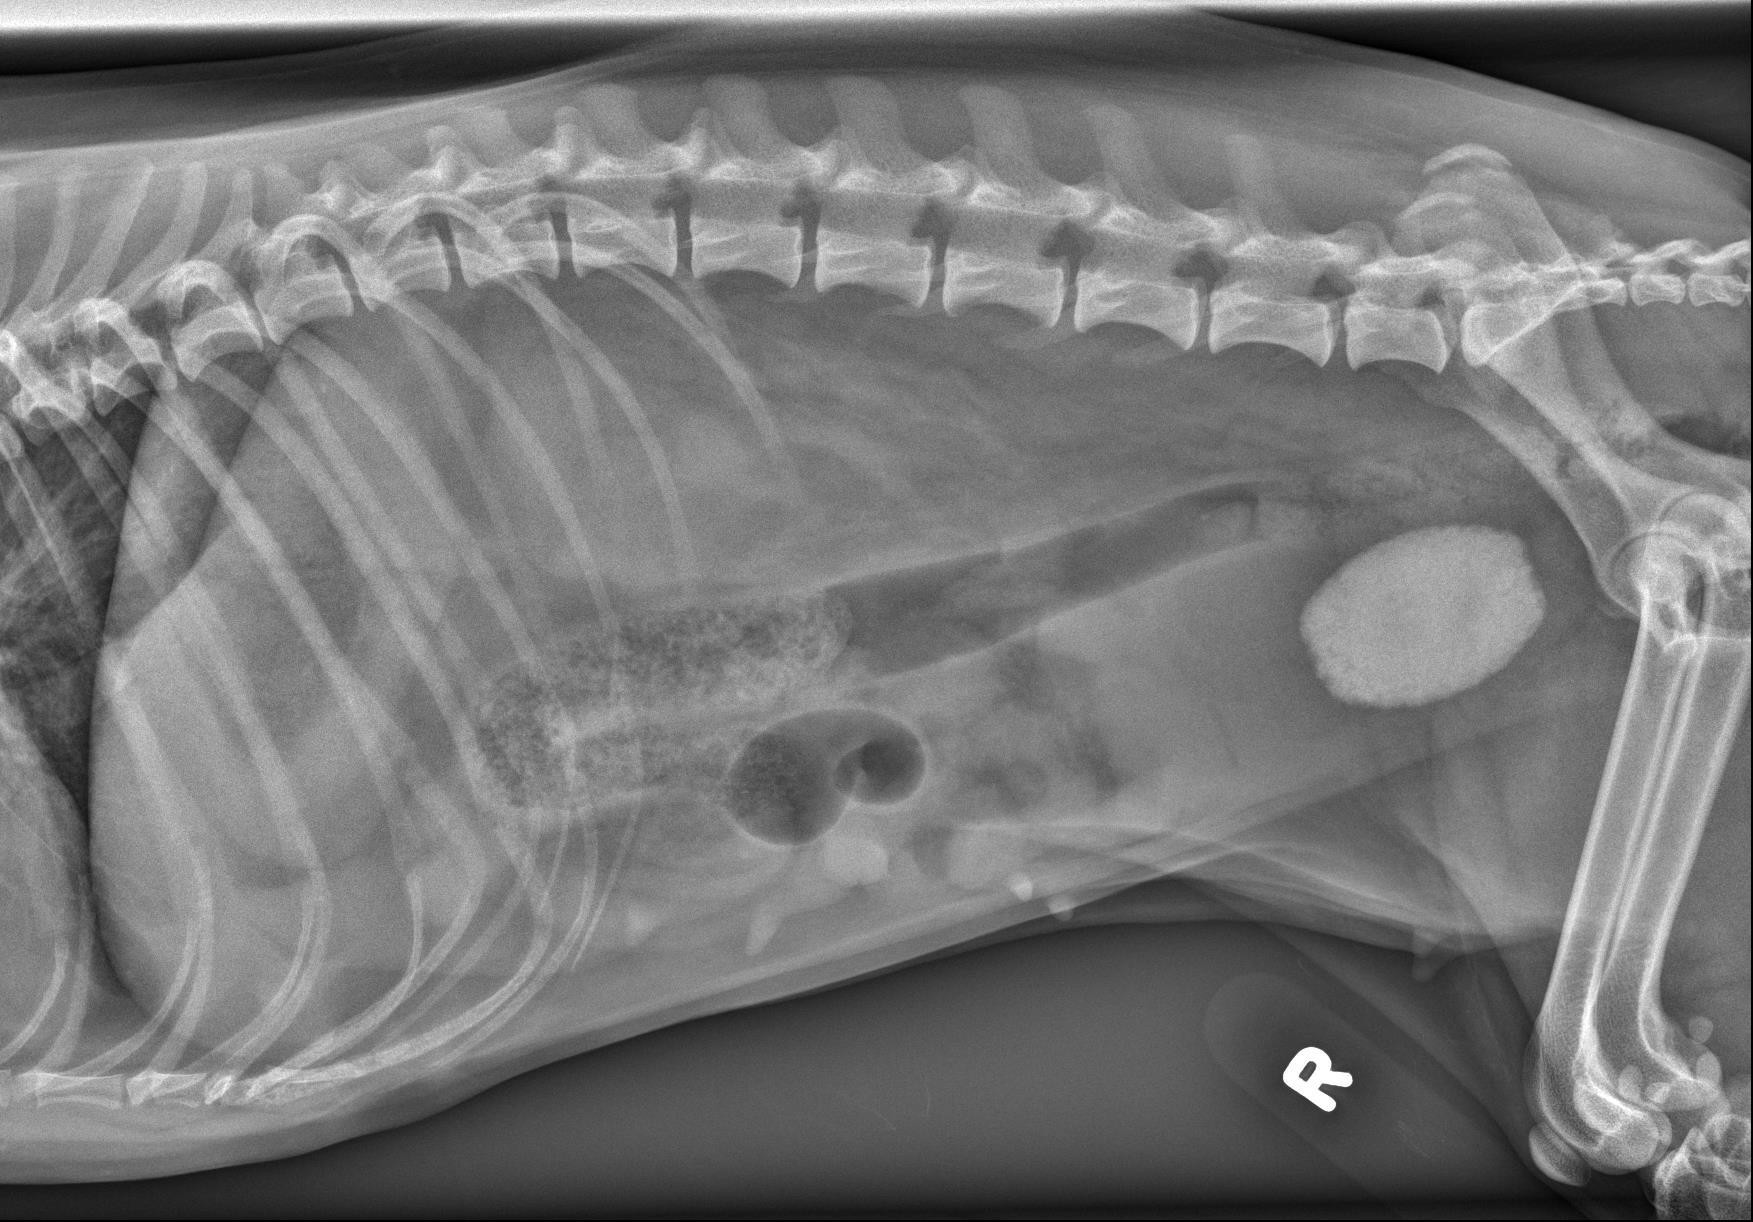

Hieronder vind je de 3 Röntgen foto’s van het abdomen. Gebruik de pijltjes om erdoor te schuiven, of klik op de foto om te vergroten.

Het retroperitoneale detail is aanzienlijk verminderd, met vloeistof-opaque strepen die de niergrenzen verdoezelen. Het peritoneale serosale detail is licht verminderd in de caudale buik, langs de craniale rand van de urineblaas.

Er is een grote, ovale, mineraal-opaque structuur net craniaal van de bekkenopening, in de regio van het trigonum van de urineblaas/proximaal van de urethra, met licht onregelmatige randen (3,6 cm in lengte en 2,5 cm in diameter). De urineblaas is matig tot sterk gedilateerd en homogeen vloeistof-opaque. De lever, milt en het maag-darmkanaal zijn normaal.

Het T8 wervellichaam is verkort en wigvormig.